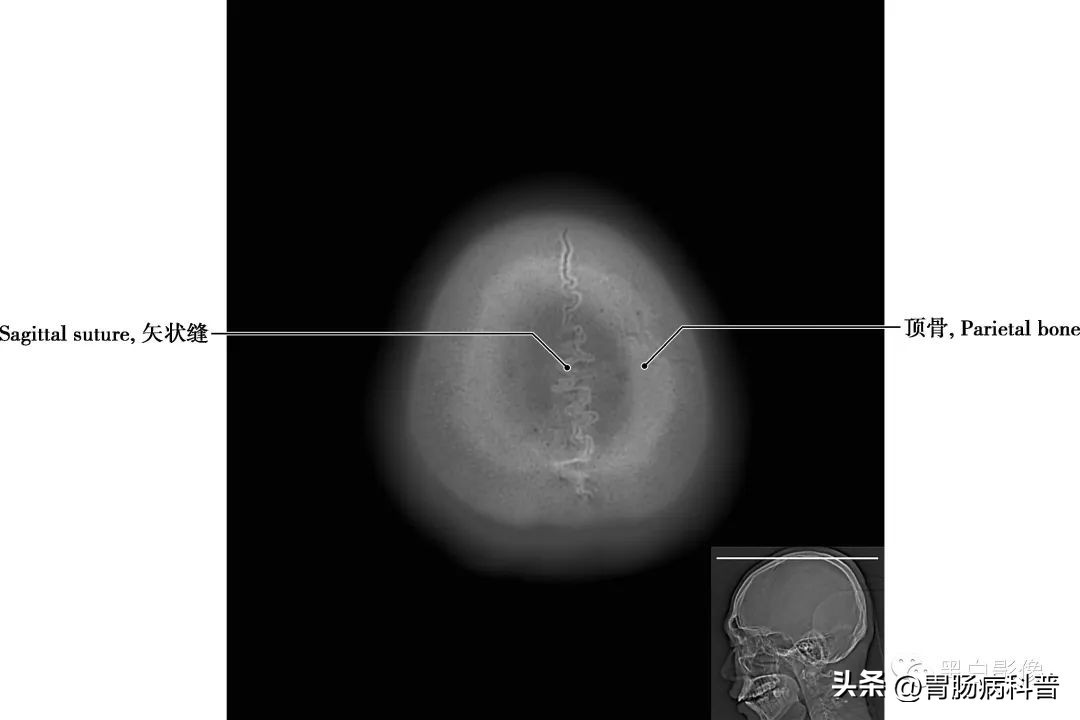

图1-2-1 经顶骨轴位切面

顶骨 位于颅盖的中部,左右各一,呈四边形,为外凸内凹典型的扁骨

图1-2-2 经上矢状窦轴位切面

矢状缝 两顶骨之间所成的缝隙,呈矢状位走行